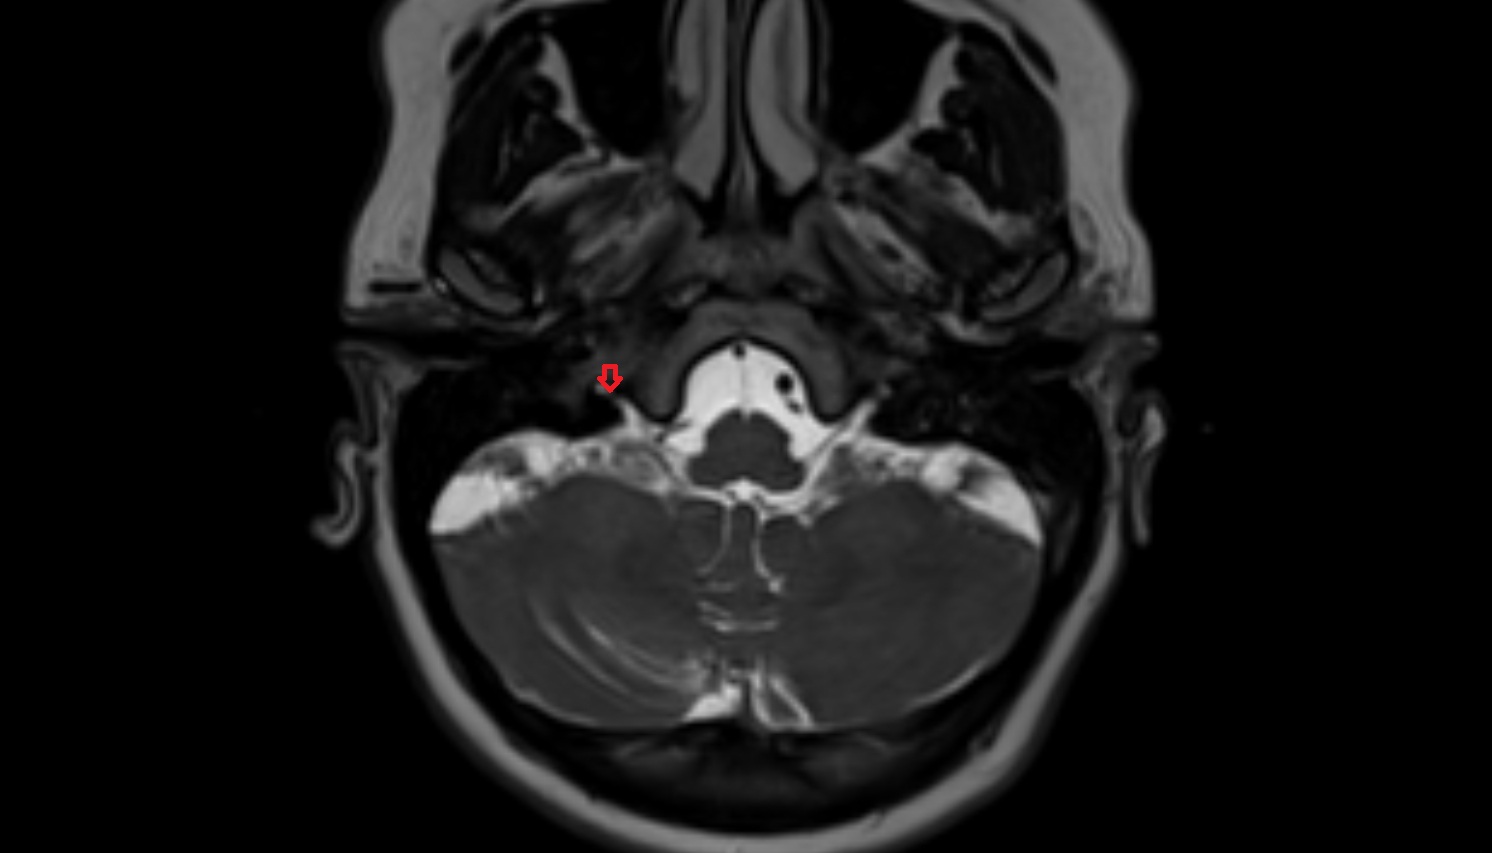

- Prepontine cistern

- Premedullary cistern

- Cerebellopontine cistern

- Cisterna magna